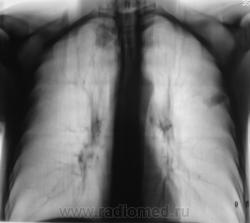

Очередной контроль после флюорографии.

Фрагменты.

без архива сложно, но похоже старые дела...

Архива нет. Человек приезжий, на ПМЖ.

Похоже, "дела давно минувших дней".